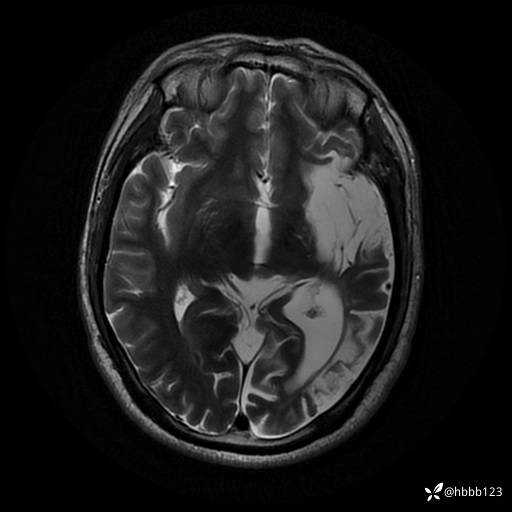

T2: